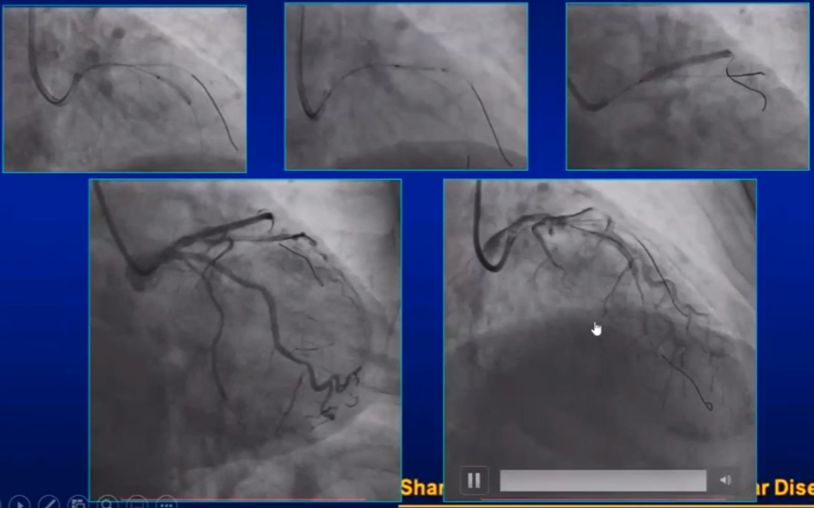

男 64岁,前壁AMI。右冠造影发现侧枝。

正位加头30再做一个, 看看侧枝。右冠看起来很怪,这时,病人发生室颤,原因是右冠导管进入的是圆锥支,圆锥支这么长时间的造影,完全堵塞的情况下发生室颤。赶紧电回来。病人马上就好了。